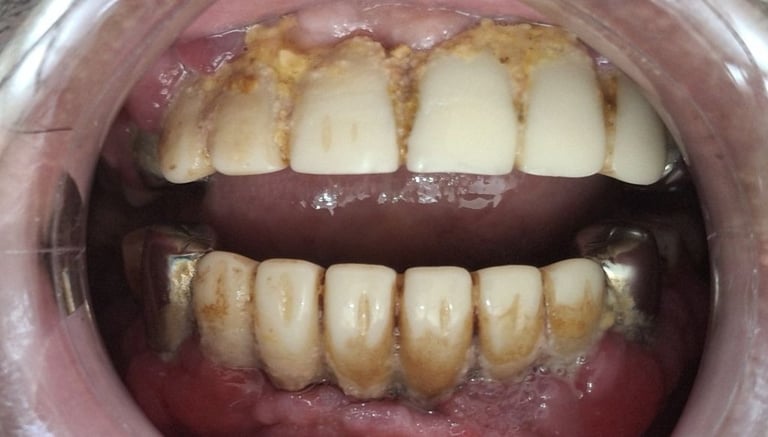

Professional Teeth Cleaning in Shyamal, Ahmedabad

Gentle, properly performed and tailored teeth cleaning for each person giving you comfort, safety and visible results. People from Shyamal and nearby areas of Ahmedabad visit our clinic for comfortable and very effective teeth cleaning.

Before

After

All images shown here are real teeth cleaning cases treated at our clinic with patient consent.

Professional teeth cleaning helps remove plaque, tarter, and surface stains that regular at home brushing can not.

At Shree Dental Care, teeth cleaning is performed gently with focus on patient experience, comfort and long term oral health.